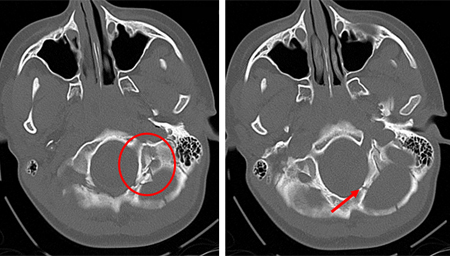

Uma história de trauma cranioencefálico (para detectar sangramento ou hematoma intracraniano)

[Figure caption and citation for the preceding image starts]: Fratura do osso temporal.Do acervo de aulas de Demetrios Demetriades, Division of Trauma and Surgical Intensive Care, LAC/USC Trauma Center, Keck School of Medicine da USC; usada com permissão [Citation ends].